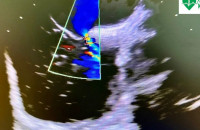

- Маленькі бульбашки — велика діагностика: у Закарпатському кардіоцентрі виконують унікальне обстеження